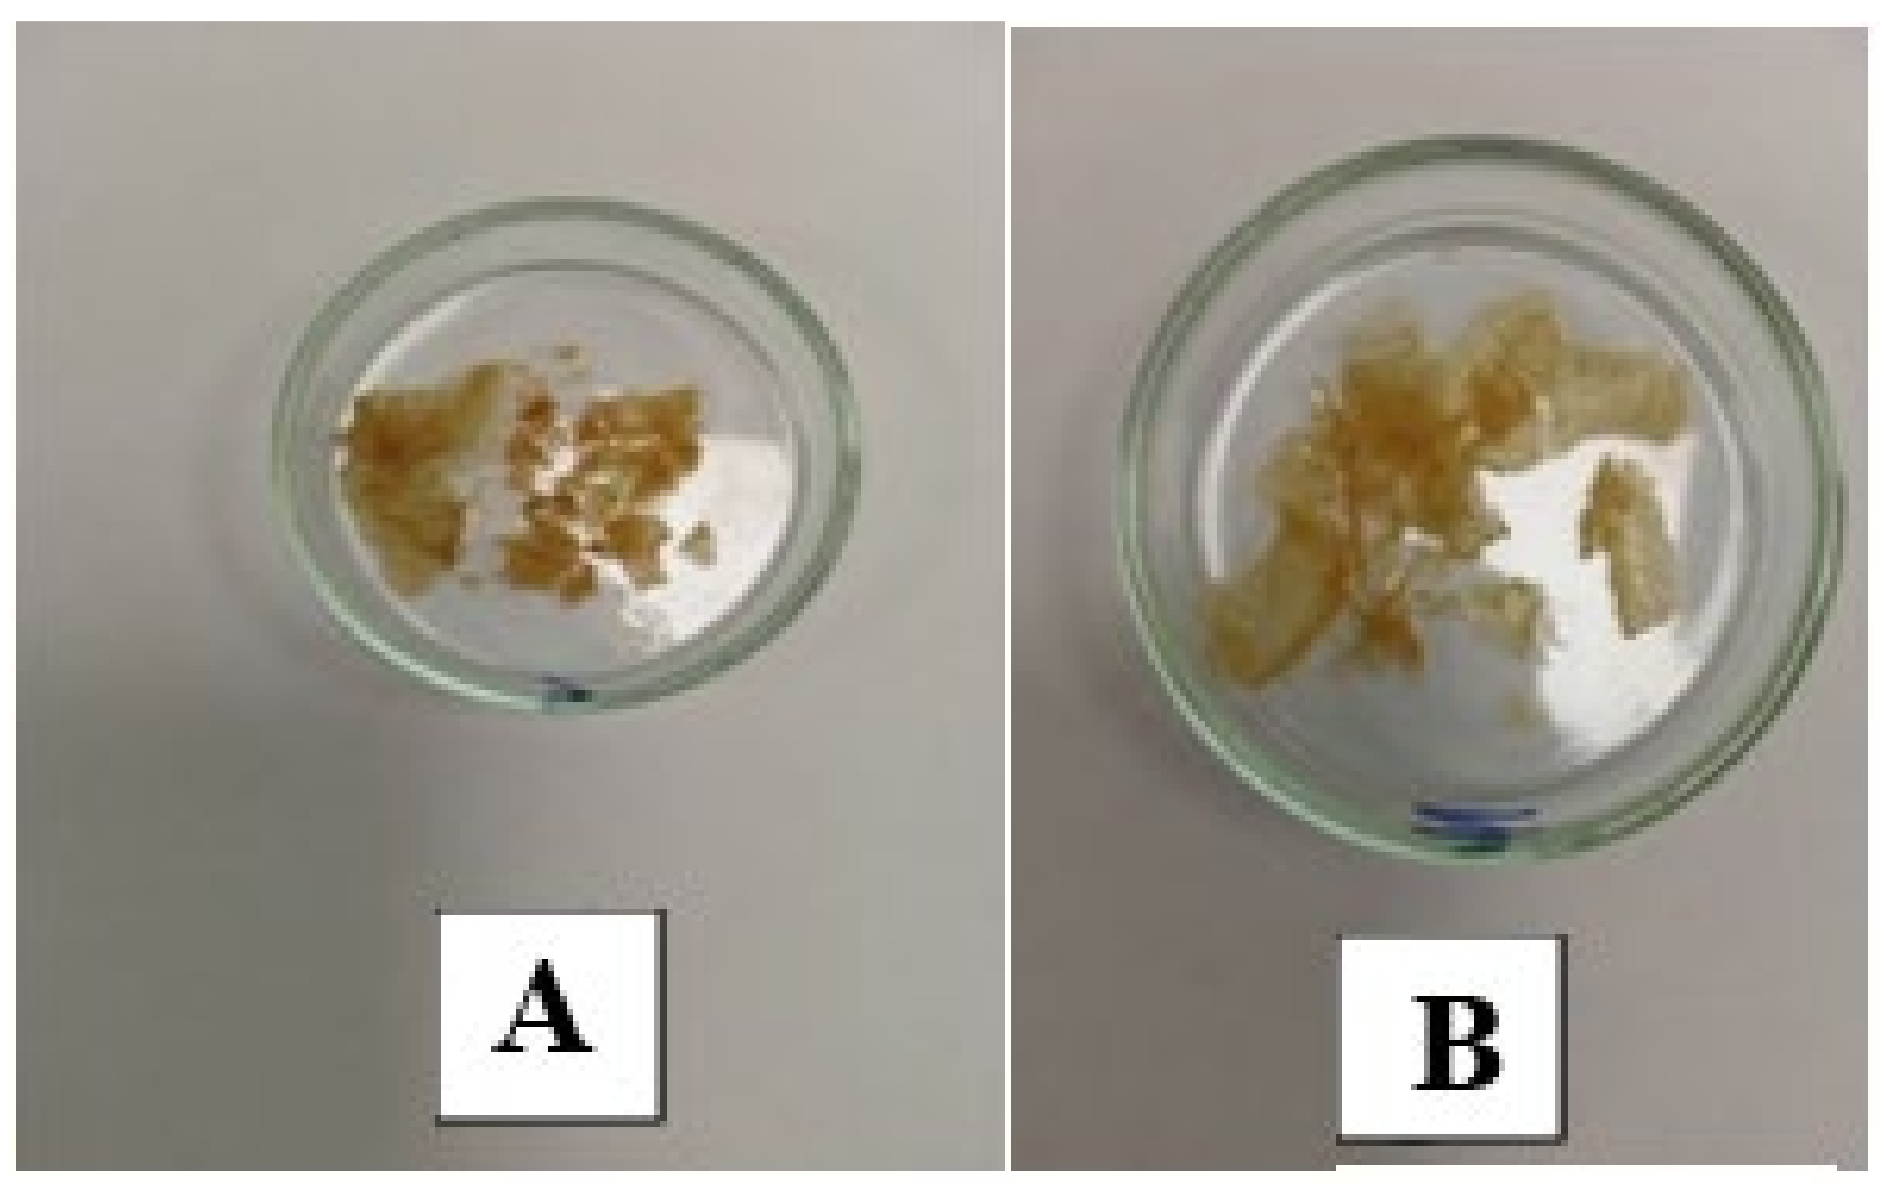

- Foreign substance (gel) migrated in the tissues, provoking the active growth of connective tissue;

- Aseptic and septic inflammatory reactions;

- Sections of round-shaped petrifications with clear contours;

- Lymphoid cell reaction, the presence of voids and necrotic masses, and the formation of cystic cavities;

- Pronounced deformation of adipocytes;

- Muscle tissue with extensive necrosis and effusion of the protein component;

- Numerous mast cells;

- Isolated, giant Pirogov–Langhans cells surrounded by lymphocytes and macrophages.